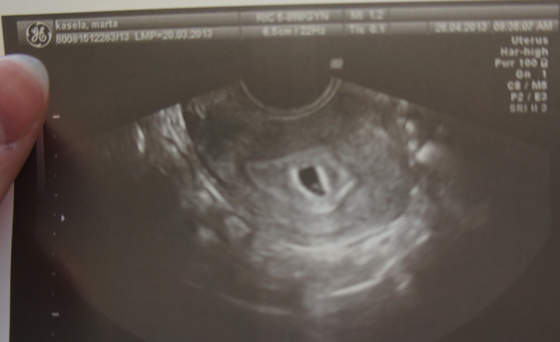

dziewczyny, nie wytrzymałam, a że mam dostęp do uSG, to oczywiście poszłam...Ale była ginka taka se, wiec tylko powiedziała,że pęcherzyk malutki, ładny i mam się nie martwić :tak:

Czy to małe na dole pęcherzyka, to moje dzieciątko? Dowiem się wszystkiego na wizycie w klinice w poniedziałek, czy wymiary dobre, itd.